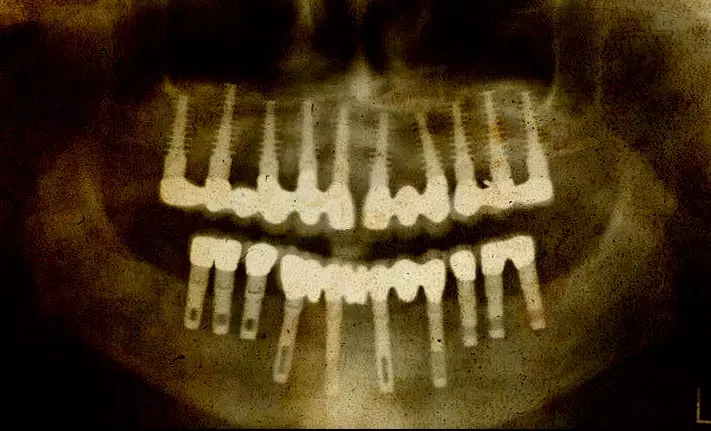

ബി.സി രണ്ടായിരത്തിലേതെന്ന് കരുതപ്പെടുന്ന ഒരു മമ്മിയുടെ പല്ലില് സ്വര്ണ്ണ കമ്പി കൊണ്ട് ഉണ്ടാക്കിയ കെട്ടാണ് ഈ ചികിത്സാരീതിയില് ഇന്ന് വരെ കണ്ടെത്തിയതില് ഏറ്റവും പഴയത്. അക്കാലത്തേത് എന്ന് തെളിയിക്കപ്പെട്ട തലയോട്ടികളുടെ കൃത്യമായ പഠനത്തിലൂടെ അന്ന് സാധാരണയായിരുന്ന ദന്തരോഗങ്ങളെപ്പറ്റി കൂടുതല് പഠിക്കാന് സാധിച്ചു. ഉമിയും തോലും പലപ്പോഴും മണ്ണിന്റെ അംശവും കലര്ന്ന ഭക്ഷണം ചവക്കുന്നത് മൂലമുണ്ടാകുന്ന പല്ലിന്റെ തേയ്മാനമായിരുന്നു ഏറ്റവും കൂടുതല് കാണപ്പെട്ട അസുഖം. ബി.സി 1200ല് ജീവിച്ചിരുന്ന എസ്കലെപിയസ് (Esculapius) എന്ന ഗ്രrക്ക് ഡോക്ടര് ആണ് ആദ്യമായി പല്ല് പറിക്കുന്ന രീതി രേഖപ്പെടുത്തിയത്.

ദന്തക്ഷയം ഉള്പ്പടെ ഇന്ന് കാണപ്പെടുന്ന പല അസുഖങ്ങളും പുരാതന കാലത്തും സാധാരണയായിരുന്നു എന്ന് കാണാം. ദന്തരോഗങ്ങളെ പറ്റിയും അവയുടെ ചികിത്സാവിധികളെപ്പറ്റിയും ഉള്ള വിവരങ്ങളടങ്ങിയ ഇബേര്സ് പാപ്പിറസ് ആണ് അറിയപ്പെടുന്ന ദന്ത ചികിത്സയെപ്പറ്റിയുള്ള ആദ്യത്തെ രേഖ. ക്രിസ്തുവിനു മുമ്പ് ജീവിച്ചിരുന്ന പ്ലേറ്റോ, അരിസ്റ്റോട്ടില് എന്നിവര് തങ്ങളുടെ രചനകളില് പല്ലുകള് മുളച്ചുവരുന്ന ക്രമം, മോണരോഗങ്ങള്, ചവണ ഉപയോഗിച്ച് പല്ല് എടുക്കുന്ന വിധം, പല്ലുകളും പൊട്ടിയ താടിയെല്ലുകള് കമ്പി കെട്ടി ഉറപ്പിക്കുന്ന വിധം എന്നിവയെപ്പറ്റി വിശദമാക്കുന്നുണ്ട്.

ഒന്പതാം നൂറ്റാണ്ടില് ജീവിച്ചിരുന്ന പ്രസിദ്ധ ദിഷഗ്വരനായ അല് റാസി പല്ലുകളിലെ ദ്വാരങ്ങള് അടക്കുന്നതിനായി വാര്ണിഷിനോടൊപ്പം ഉപയോഗിക്കുന്ന തരം മരപ്പശയും (mastic) ആലവും കലര്ന്ന മിശ്രിതം ഉപയോഗിച്ചിരുന്നു. എല്ലാ സാധ്യതകളും അടഞ്ഞാല് മാത്രമേ പല്ല് പറിക്കാന് തീരുമാനിക്കാന് പാടുള്ളു എന്നദ്ദേഹം അഭിപ്രായപ്പെട്ടു. മോണ പഴുപ്പിനായി അദ്ദേഹം ഓപിയം, റോസ് ഓയില്, കുരുമുളക്, തേന് എന്നിവ ഉപയോഗിച്ചിരുന്നതായി കാണുന്നു. പത്താം നൂറ്റാണ്ടിലെ പ്രസിദ്ധ ഭിഷഗ്വരനായ അവിസീന തുടര്ച്ചയായി വേദനയുള്ള പല്ലുകള് തുരന്ന് വൃത്തിയാക്കി അതില് മരുന്ന് നിറക്കുന്നതിനെപ്പറ്റി പറയുന്നുണ്ട്. പതിനൊന്നാം നൂറ്റാണ്ടില് ജീവിച്ചിരുന്ന അബുല് കസെയ്സിന്റെ പുസ്തകത്തിലാണ് അക്കാലത്ത് ദന്ത ചികിത്സക്കായി ഉപയോഗിച്ചിരുന്ന ഉപകരണങ്ങളുടെ ചിത്രങ്ങള് ആദ്യമായി പ്രസിദ്ധീകരിച്ചത്. വീഴ്ചയുടെ ഫലമായി ഇളകി പോയ പല്ലുകള് അതത് സ്ഥലങ്ങളില്തന്നെ കമ്പി കൊണ്ട് കെട്ടി ഉറപ്പിക്കുന്ന വിധവും ഇതില് വിവരിക്കുന്നു.